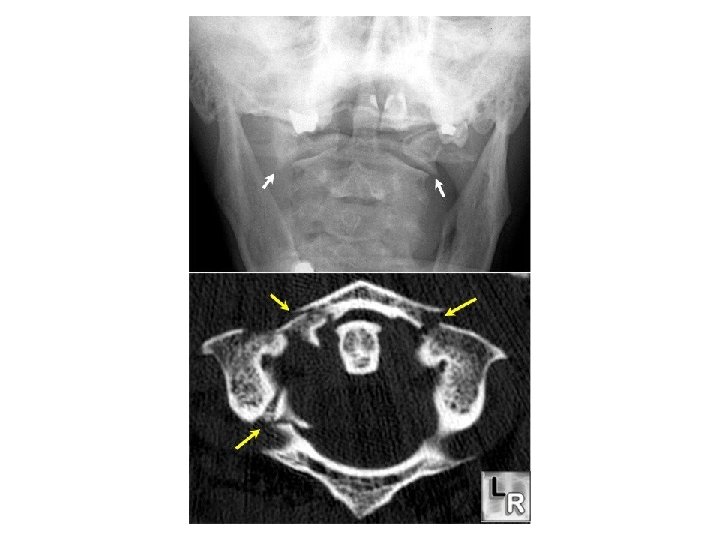

JEFFERSON FRACTURE • Burst type fracture of C 1 • Lateral displacement of C 1 masses • Fracture of anterior and posterior arches on both sides – quadruple fracture • Unstable – transverse ligament rupture • Soft tissue swelling is marked on Xray